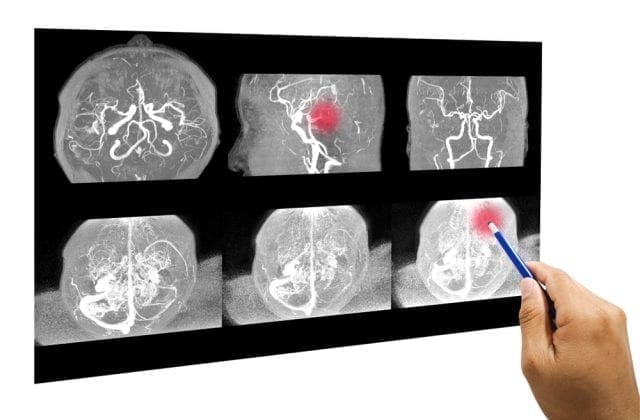

Understanding brain tumor growth opens door for non-surgical treatment

Understanding brain tumor growth opens door for non-surgical treatment. One in 25,000 people worldwide is affected by neurofibromatosis type 2 (NF2), a condition where the loss of a tumor suppressor called Merlin results in multiple tumors in the brain and nervous system.

Sufferers may experience 20 to 30 tumors at any one time and such numbers often lead to hearing loss, disability and eventually death. Currently, the only available effective therapies are repeated invasive surgery or radiotherapy aimed at one tumor at a time and which are unlikely to eradicate all the tumors in one go. NF2 can affect any family, regardless of past history, through gene mutation. There is no cure.